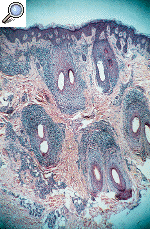

--La otra biopsia fue tomada de una de las placas de alopecia de cuero cabelludo. Presentaba un infiltrado linfohistiocitario perifolicular que afectaba a los dos tercios superiores de los folículos (Fig. 4 A), destruyendo la capa basal de la vaina externa folicular con formación de cuerpos coloides (Fig. 4 B).

FIG. 4.--A: Infiltrado linfohistiocitario perifolicular que afecta a los dos tercios superiores de los folículos. B: Destrucción de las capas periféricas de la vaina externa por el denso infiltrado linfocitario.